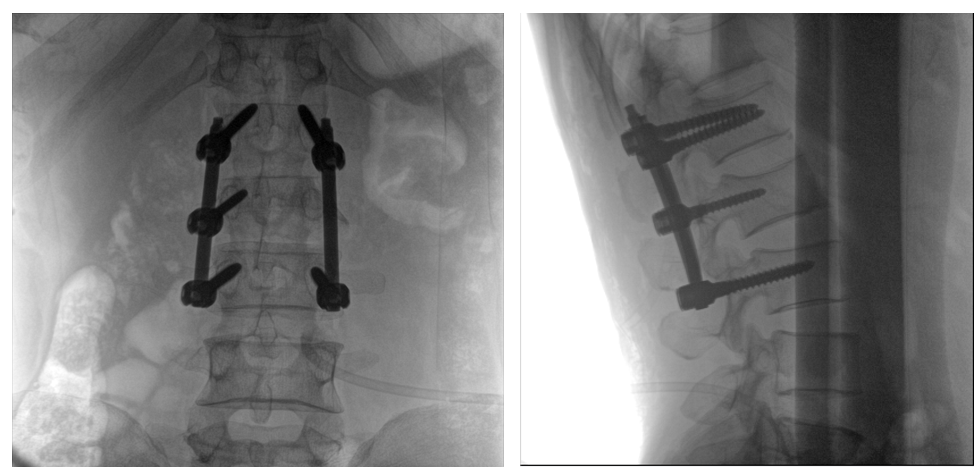

病例一:

患者不慎摔傷,傷后腰部疼痛,腰2椎體壓縮性骨折,遂以“椎弓根釘內固定術”治療。椎弓根螺釘可以從椎體后方貫穿到椎體前方,達到椎體三柱固定,但是手術過程中要保對多節(jié)錐體進行手術,所以要求圖像要盡可能的展現(xiàn)出全節(jié)段腰椎。

一體式C形臂全節(jié)段腰椎臨床影像

普愛醫(yī)療PLX119C大平板一體式C形臂采用30CM×30CM的平板探測器,一般可一次性成像5節(jié)腰椎,呈現(xiàn)更廣闊的視野。使醫(yī)生一次性全面地觀察到傷椎及周圍椎體情況,使得手術效率更高、更準確。